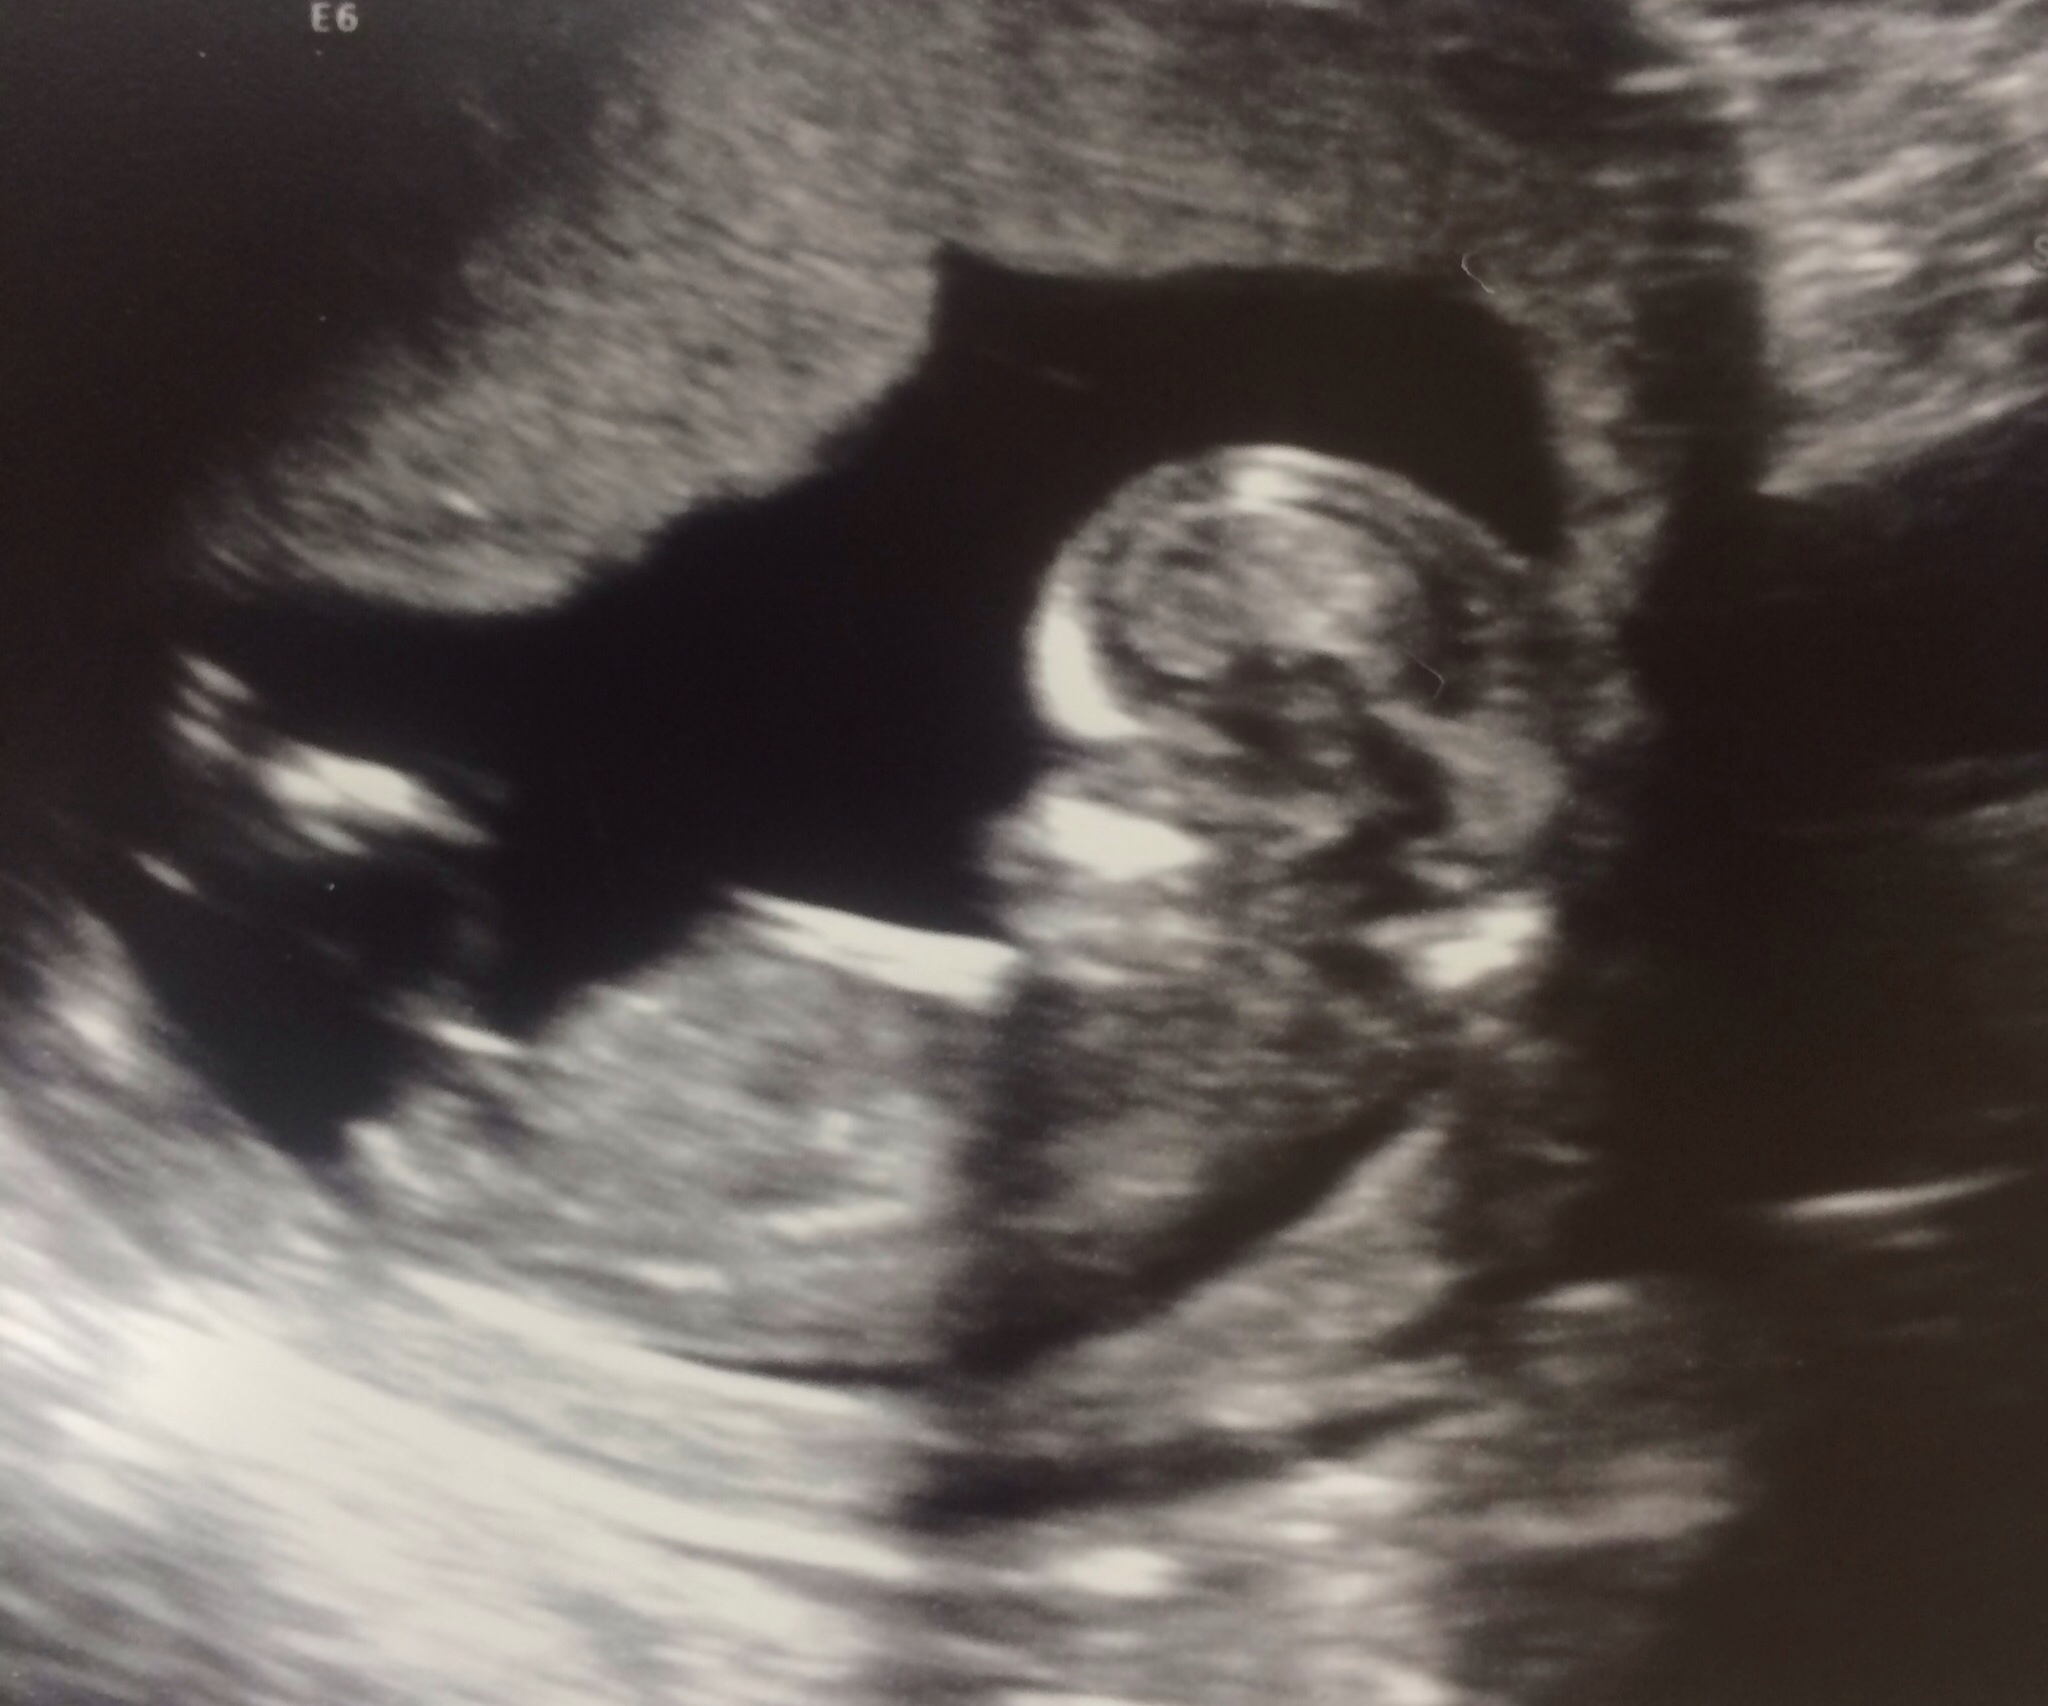

Baby is a bit too curled for my liking in both the shots that show any nub-action. My first thought was boy because of the end of the top nub. But given the curled baby, I wonder if I am seeing that because of how the spine is. I can't say I am leaning strongly either way. Sorry!

Is the nub too low in the first one?